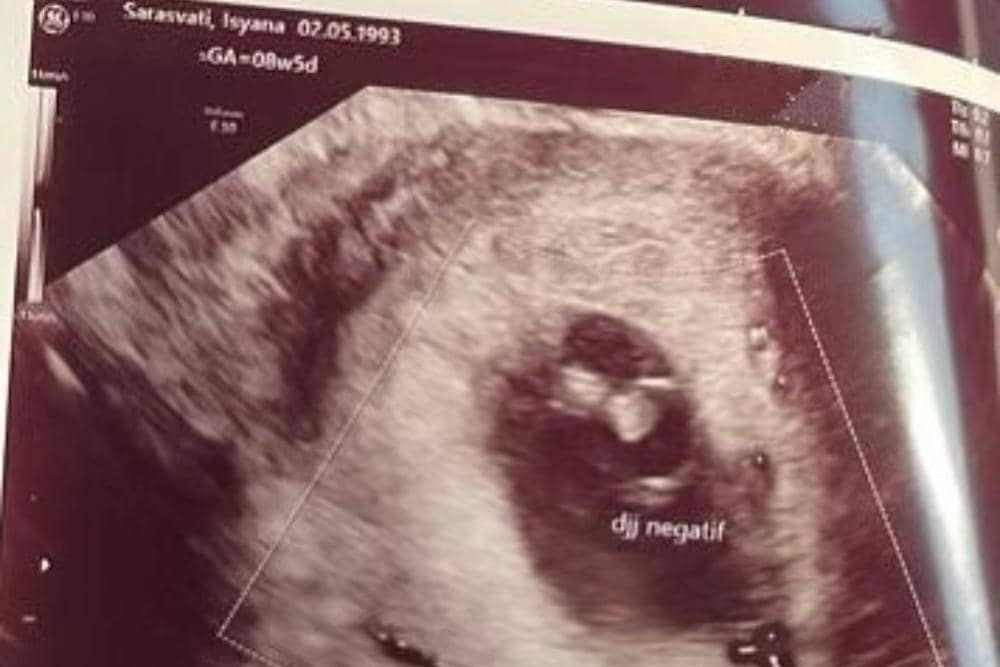

Unggah foto USG

Kabar duka dibagikan langsung lewat Instagram feeds Isyana. Dengan foto hitam dan emoji bunga mawar yang layu, Isyana menyematkan foto USG di slide selanjutnya.

Dalam foto tersebut, terlihat keterangan 'djj negatif'. Djj sendiri merupakan singkatan dari 'detak jantung janin'. Itu artinya, hasil foto USG tersebut menunjukkan bahwa janin yang ada di dalam kandungan Isyana sudah tidak memiliki detak jantung atau telah meninggal.

Kemudian, jika diperhatikan lebih lanjut, terlihat pula usia kehamilan Isyana. Pada foto itu, tertera keterangan '08w5d' yang menunjukkan kehamilan Isyana telah memasuki usia 8 minggu 5 hari.